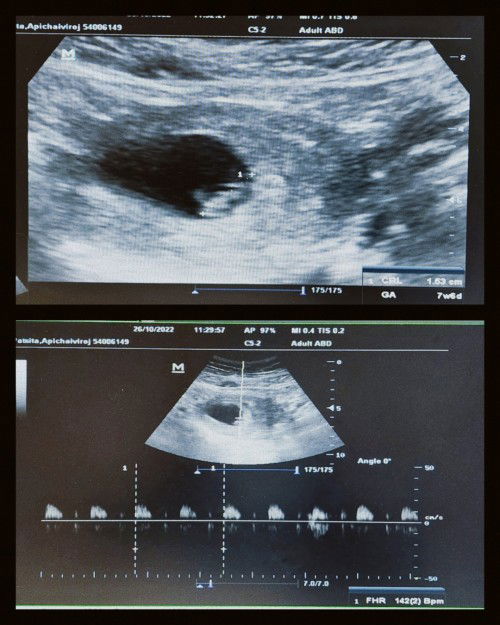

เราเป็นคุณแม่ท้องแรกค่ะ วันนี้ไปตรวจครั้งที่สองกับคุณหมอมาค่ะ ครั้งเเรกไปตอน 5week 3 เห็นเเค่ถุงตั้งครรถ์ คุณหมอซาวน์ดูว่าถุงอยู่ในมดลูกไหม ได้เจาะเลือดตรวจพาหะ ธาลัสซีเมีย โรคติดต่อ ความสมบูรณ์ของเลือดทั้งพ่อและเเม่ วันนี้ 7week6 นัดฟังผลเลือดปกติดีทุกอย่าง ได้ เห็นตัวน้องเเล้วค่ะได้ยินเสียงหัวใจน้องด้วยดังชัดมากๆ ตื่นเต้นเเละ ดีใจมากเลยค่ะ ❤️ #ท้องแรกคะ